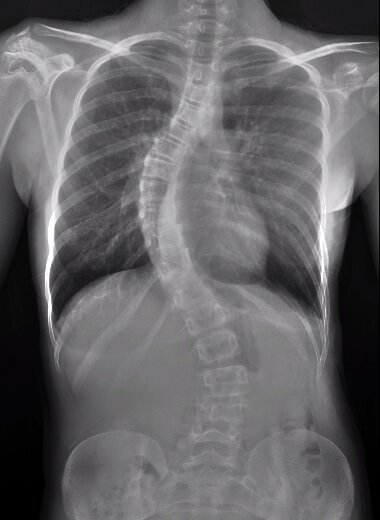

And not just a little out of place. "My curvature was 60 or more degrees," she said. X-rays showed her spine was curving into an "S" shape.

Susan's spine before surgery